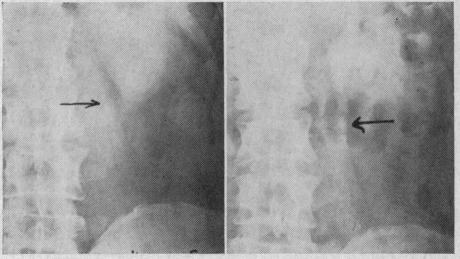

Immediate steps in the treatment of ureteral stone, beginning with the often acute onset, are relief of pain, urinalysis (including Gram stain), forcing fluids, examination of urine for the stone and urography at the earliest feasible time. If the stone causes continual pain or appears unlikely to be passed safely, it should be removed-with a cystoscope if possible; if not, by operation which may be done while the patient is still under anesthesia. To combat further stone formation a large fluid intake should be maintained, the extracted stone analyzed, an acid ash diet prescribed, serum calcium and phosphorus measured, urinary stasis corrected and urinary infection and distant foci of infection cured. Vitamin A, aluminum gels and particularly hyaluronidase appear promising as preventives to stone formation.